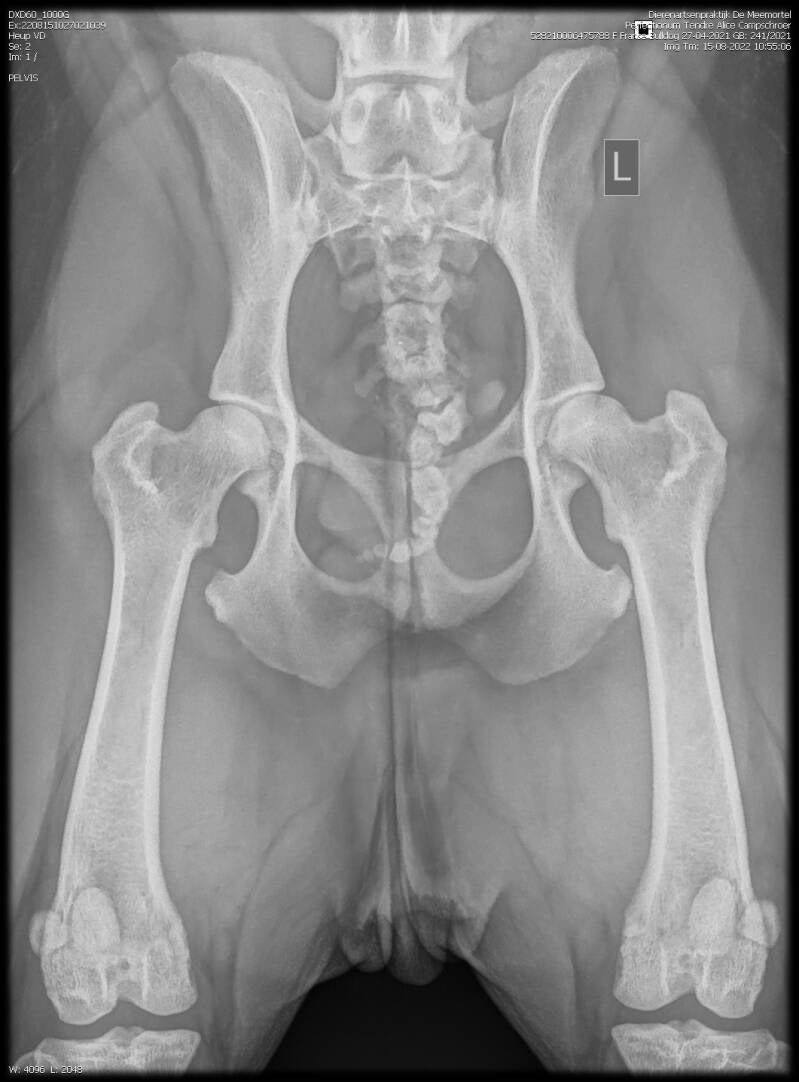

Perfectionum Tendre : Alice ( Brit) 27-04-2021

Brit is uit ons A een dochter van Loes

HD: beiden A.

ED: vrij.

Atrose: vrij.

CFR 0,30